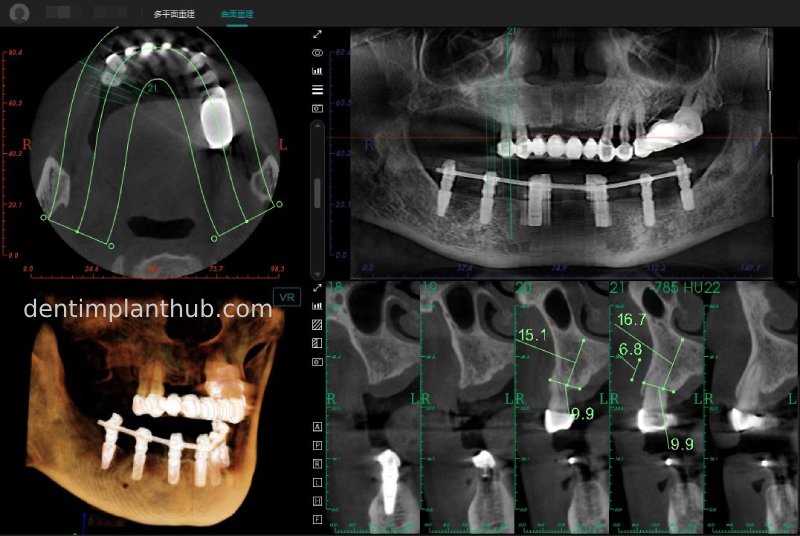

A review of the CBCT on 6/10/23 was more promising and a surgical plan was subsequently drawn up.

46

44

42

32

34

36

General schematic of the surgical programme

Detailed list of implant types and composite abutments to be prepared.

46 tooth position, implant model number 4810, RC series straight composite abutment;

44 tooth position, implant model number 4110, RC series straight composite abutment;

42 tooth position, implant model number 4110, RC series straight composite abutment; alternate implant model number 3310, alternate NC series straight composite abutment;

32 tooth position, implant model number 4110, RC series straight composite abutment; alternate implant model number 3310,. Alternate NC Series Straight Composite Abutment;

34 Dental Position, Implant Model No. 4110, RC Series Straight Composite Abutment;

36 Dental Position, Implant Model No. 4808, RC Series Straight Composite Abutment;